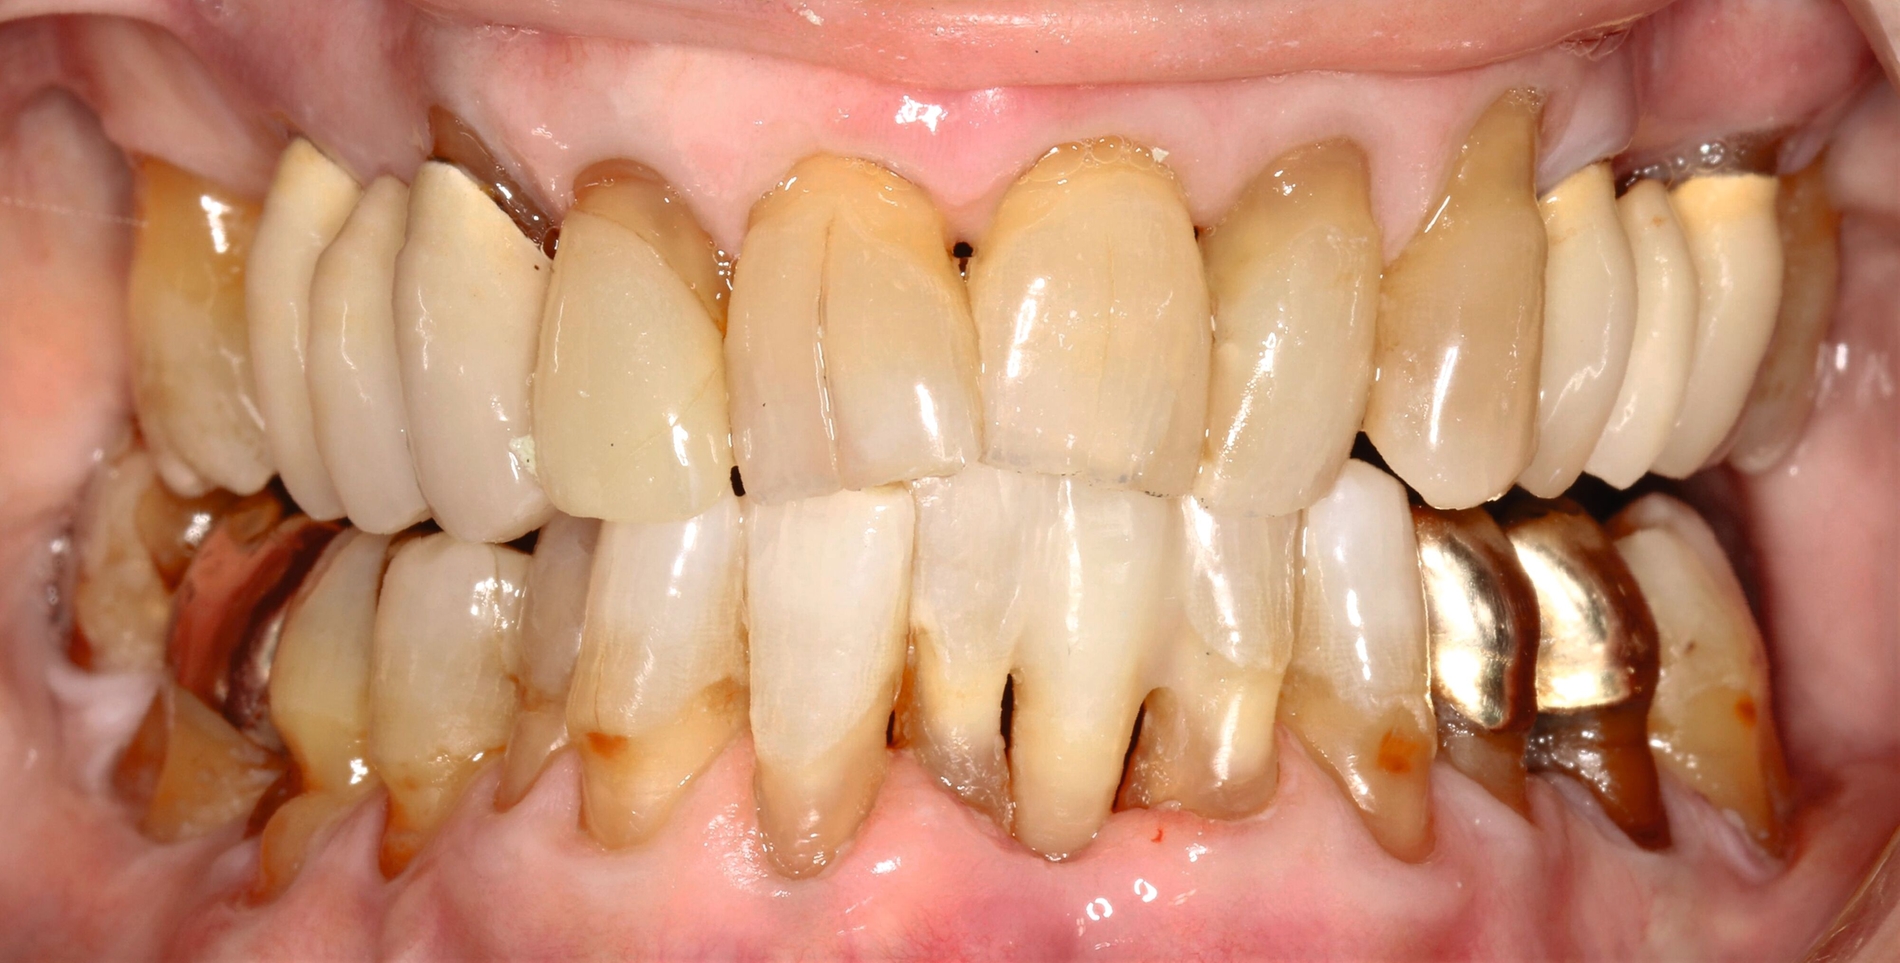

Da anhand eines Zahnfilms festgestellt worden war, dass der Zahn 31 – vermutlich aufgrund einer Paro-Endo-Läsion – eine apikale Aufhellung zeigte, war bereits die Extraktion mit anschließender Umarbeitung und adhäsiver Wiedereingliederung des extrahierten Zahnes als Option angesprochen worden. Kurz vor dem vereinbarten Eingriff meldete sich die Patientin telefonisch, um sich zu erkundigen, ob sie den Termin denn überhaupt noch benötige, da der betroffene, gelockerte Zahn 31 in der Unterkieferfront beim Essen von selbst herausgefallen sei und sie ihn bereits entsorgt habe. Schmerzen, eine Schwellung oder Nachblutungen verneinte die Patientin. Sie wurde gebeten, den vereinbarten Termin am Folgetag dennoch wahrzunehmen, mindestens zur Kontrolle der Wunde, gegebenenfalls zur Planung der Weiterversorgung (Abbildungen 5 und 6).

Nach der erneuten Untersuchung am Folgetag wurden der Patientin die möglichen Therapieoptionen in der neu entstandenen Situation erläutert. Denkbar waren grundsätzlich ein prothetischer Ansatz, aus konservierender Sicht der Lückenschluss mittels adhäsiver Zahnverbreiterung und der Lückenschluss mittels Ersatzzahn.

Bei hochbetagten Patientinnen und Patienten mit gegebenenfalls weiteren gesundheitlichen Einschränkungen und einer geringeren Adhärenz kommt auch eine Therapia nulla in Betracht. Aufgrund der wegen der Lockerung der Unterkieferfront sinnvollen parodontalen Schienung entschieden sich die Patientin und der Behandler für den Kunststoff-Prothesenzahn zum Lückenschluss – mit dem Vorteil einer insgesamt relativ kurzen Behandlungsdauer, was der Patientin aufgrund der Wirbelsäulenarthritis entgegenkam. Ebenso ist diese Behandlungsvariante wenig invasiv und hätte auch substanzschonend wieder entfernt werden können.